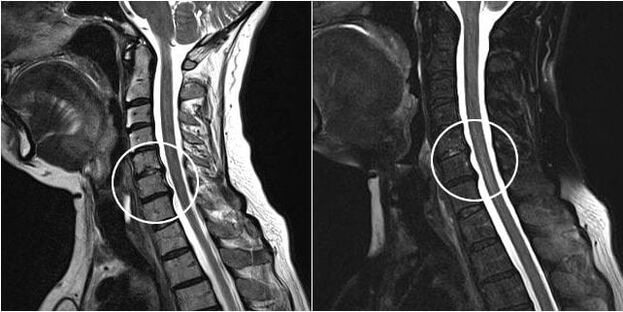

As indicacións para a intervención cirúrxica inclúen a ineficacia do tratamento conservador, así como as complicacións da osteocondrose cervical, por exemplo, a mielopatía discoxénica, a síndrome da arteria vertebral e a síndrome radicular. Para descomprimir a medula espiñal, os vasos sanguíneos e as raíces da columna, realízanse as seguintes operacións: